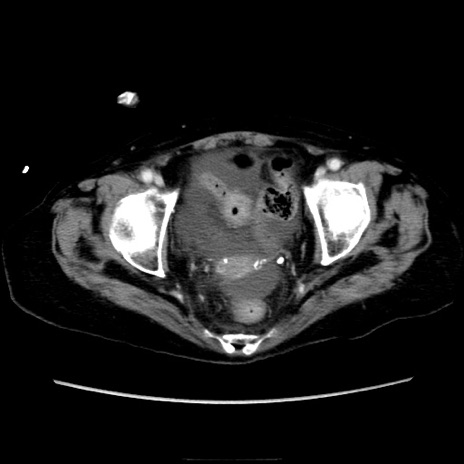

症例40(横断像)

【症例】90歳代女性

【主訴】腹痛・嘔吐

【現病歴】 食欲低下、嘔吐があり昨日他院受診。肺炎と診断され入院となる。入院後より腹部全体に圧痛あり。胃管留置され経過みていたが、症状持続するため、

当院転院となる。

【既往歴】胸椎圧迫骨折、胆石症

【身体所見】腹部:中央に激痛あり、圧痛あり、反跳痛不明

【データ】WBC 17100、CRP 18.82

横断像